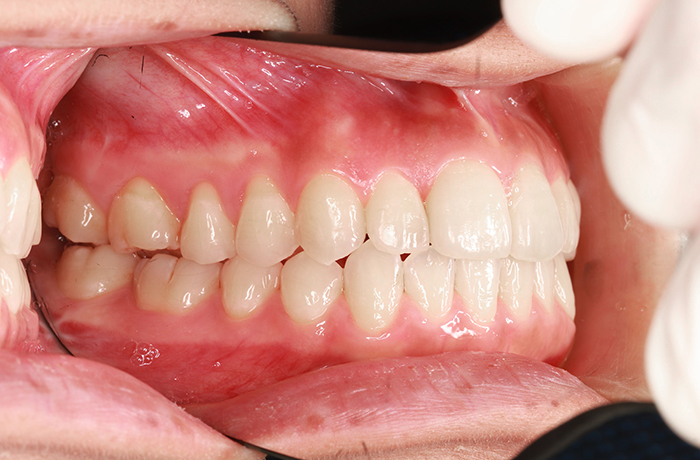

after

年齢 21歳

性別 男性

治療名称 マウスピース型カスタムメイド矯正歯科装置(インビザライン)・コンプリヘンシブパッケージ(フルパッケージ)

総額治療費用 770,000円(税込10%) 金額備考 精密検査料・診断料 33,000円(税込10%)

治療期間 1年 通院頻度など 1か月ごと

その他治療に関する情報

治療内容

患者の症状 上顎前突、前歯離開

治療方法 マウスピース型カスタムメイド矯正歯科装置(インビザライン)による矯正

治療結果 歯列改善、咬合状態が良くなりました。

※治療結果は患者様によって個人差があります。

治療を行う上での注意点

リスク/副作用 20時間以上、装置の装着時間が必要です。